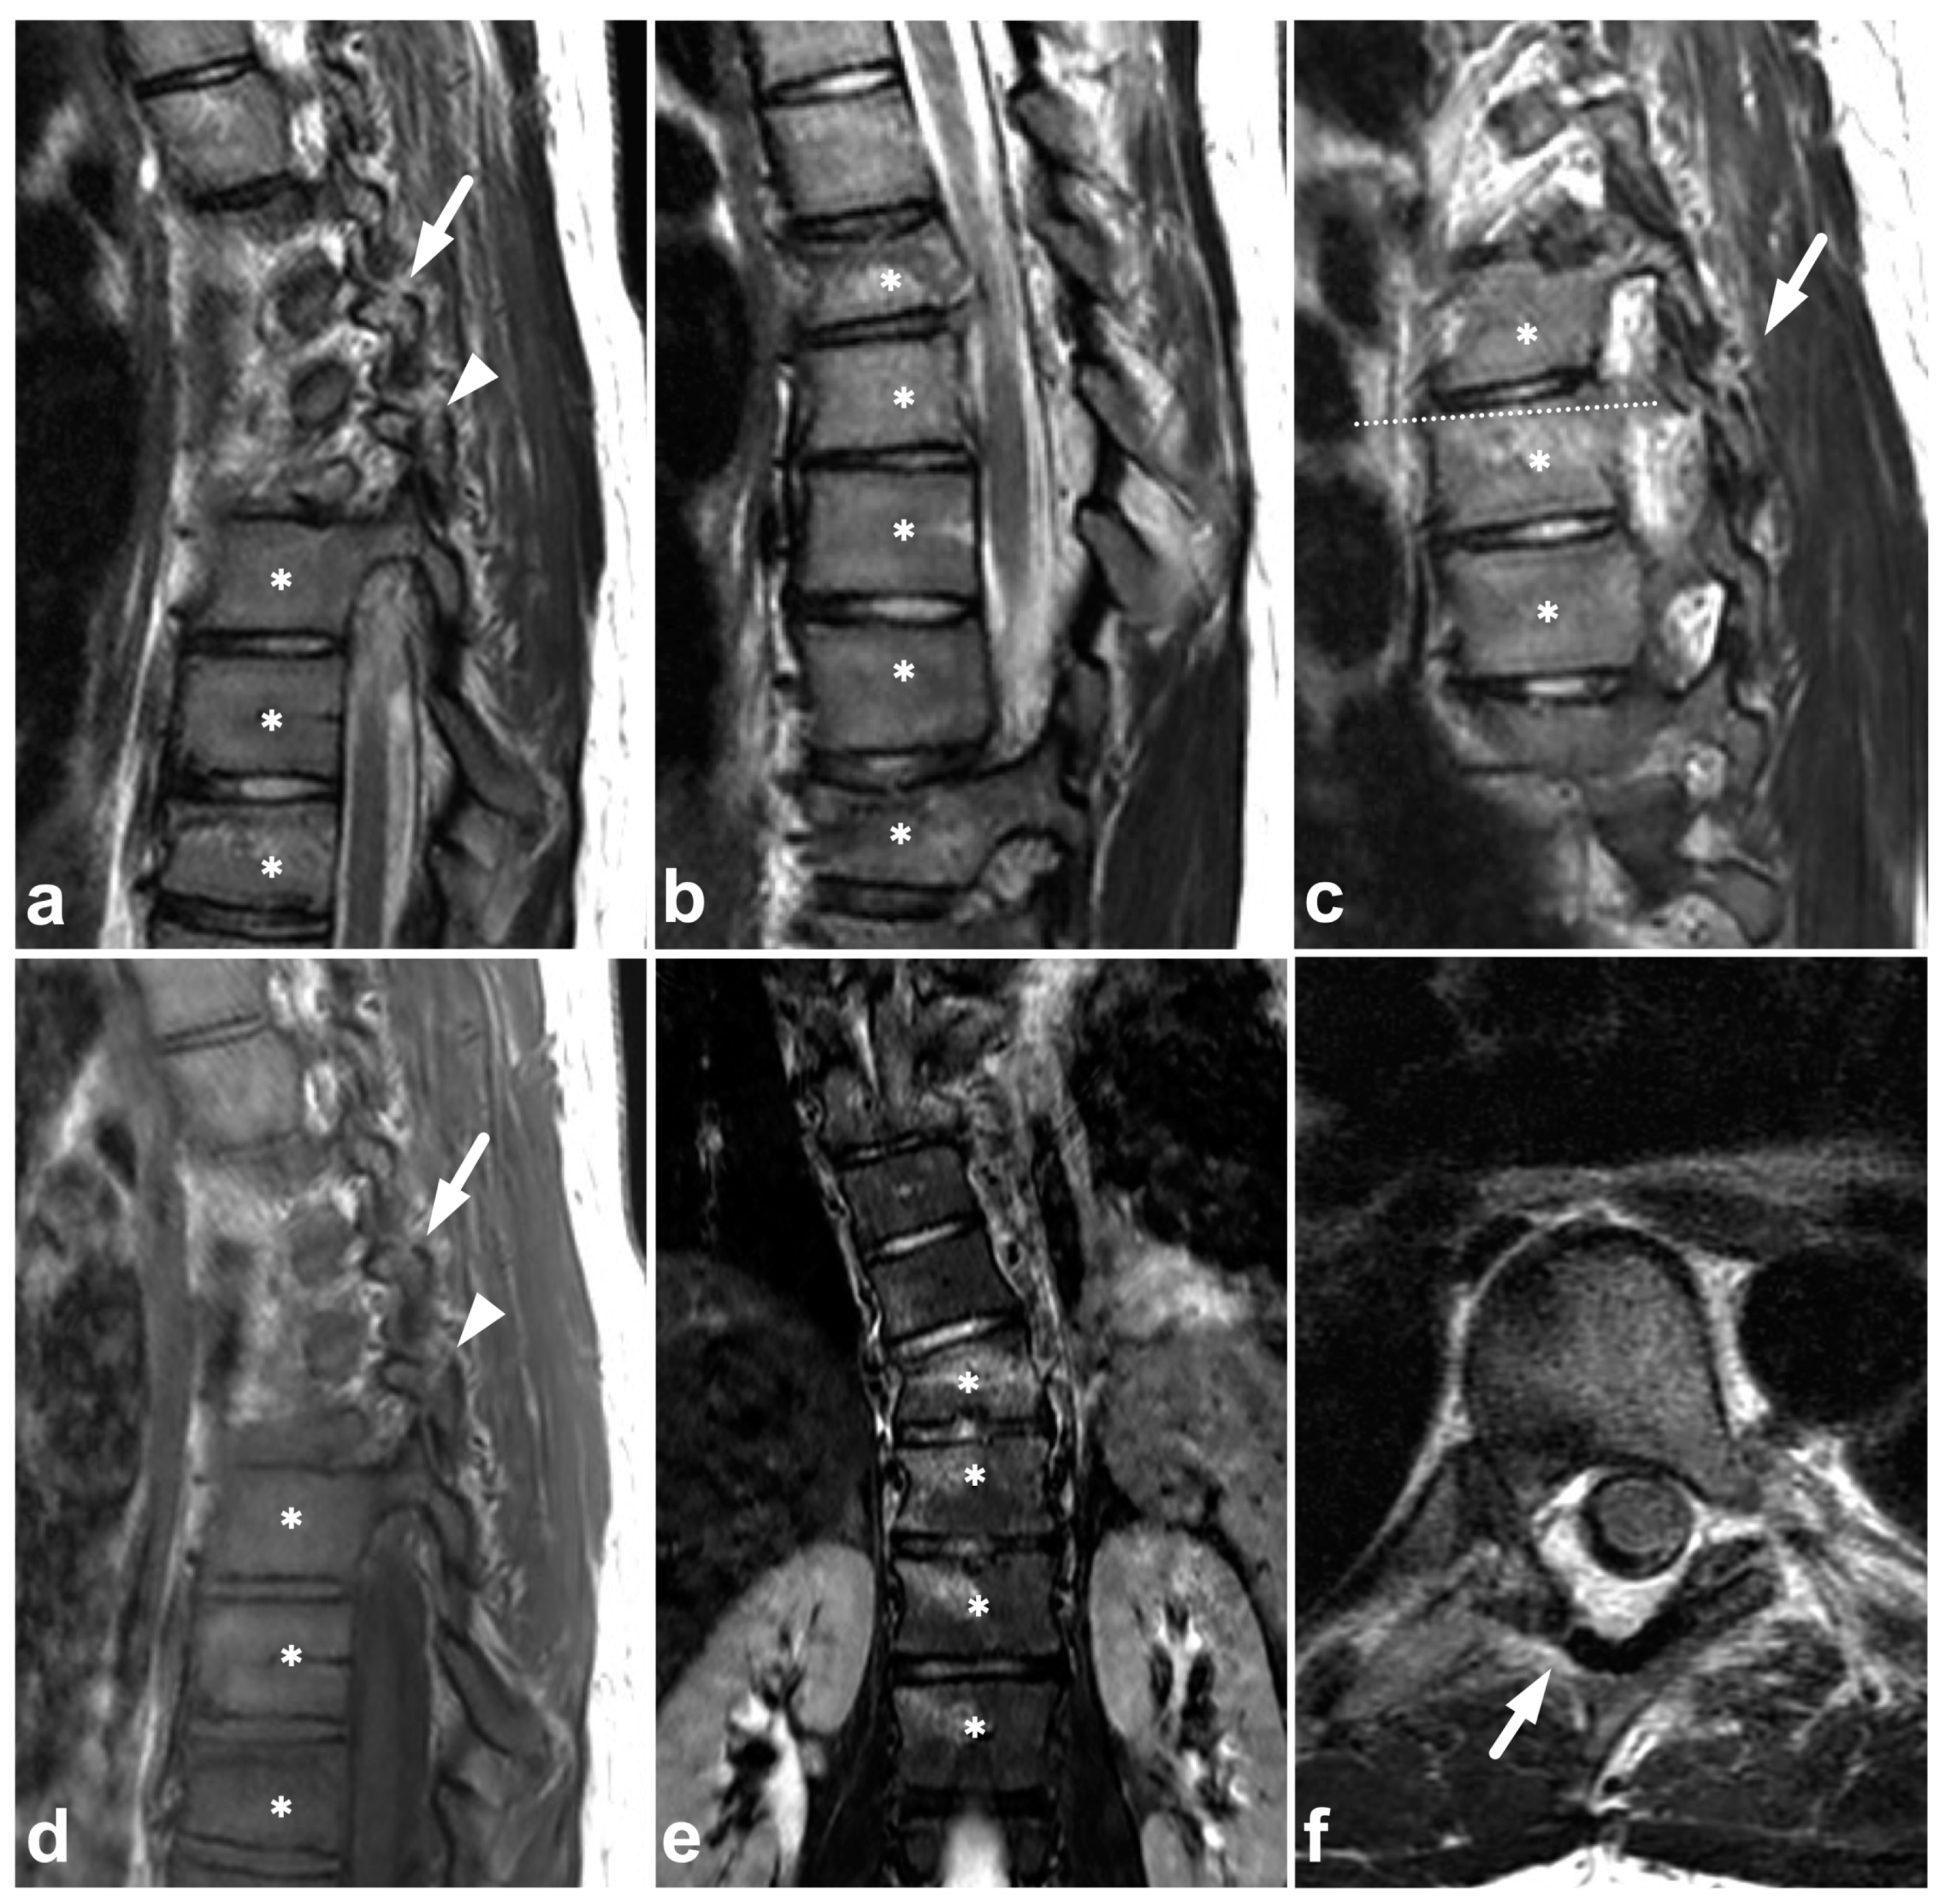

4.2. Posterior Ligament Complex

The posterior ligament complex (PLC) consists of the ligamentum flavum, interspinous ligament, supraspinous ligament, and facet joint capsules. It is noted as an essential factor for spinal stability in numerous classification systems proposed for spinal trauma [42]. Of these classifications, the TLICS [43,44,45] and AO Spine systems [43,46,47,48] have also been found to have good interrater reliability in the pediatric population. Dawkins et al. [44], however, concluded the interrater reliability of the TLICS classification to be lower with patients having undergone MRI than those treated based on CT imaging only. As the authors discussed, this is probably explained by MRI’s superior sensitivity in demonstrating stable PLC injuries that would be undetectable in CT or plain radiographs. It is possible that the MRI’s suggested poor interrater reliability with the TLICS classification could be improved with education, given that, in the study by Dawkins et al., spine surgeons with varying experience read the MRIs, and no radiologists were involved.

In addition to a widened interspinous distance and other indirect measures used with CT and plain radiographs, MRI can differentiate the very components of the PLC, revealing the culprits responsible for the indirect CT findings (Figure 9).

Figure 9.

(a) Sagittal STIR. (b) Sagittal T2-weighted. (c) Sagittal T1-weighted. (d,e) Axial T2-weighted, two adjacent slices at the level C6/7 (line on the image (c)). (f) Right-sided off-midline sagittal STIR. (g) Coronal STIR. (h) Left-sided off-midline sagittal STIR. A 9-year-old female, flexion injury in a trampoline accident. On level C2/3, there is slight edema in the posterior atlantoaxial membrane (PAAM), rectus capitis posterior major muscle, nuchal ligament, and adjacent deep cervical fat tissue (small white arrows). On level C6/7, we see more prominent edema of the interspinous and supraspinous ligaments (white arrows); there is a partial tear in the interspinous ligament. At this level, the ligamentum flavum is inhomogeneous (black arrowheads) due to a partial tear but without loss of continuity. A thin hematoma can also be seen between the flavum and posterior arch of C7 (white arrowheads, image (d)). Minor facet joint injury is also present; a small amount of fluid and edema can be seen at the left C2/3 facet joint and the posterior parts of both facet joints at level C6/7 (angled arrows). In addition to the PLC injury, there are compression fractures at the anterior parts of the vertebral bodies C7/Th3 (white asterisks). This is also a typical finding in flexion injuries of the cervical spine. The findings presented are highly unlikely to lead to instability, demanding a surgical fixation. However, this case demonstrates MRI’s power to directly assess the different stabilizing structures of the spine.